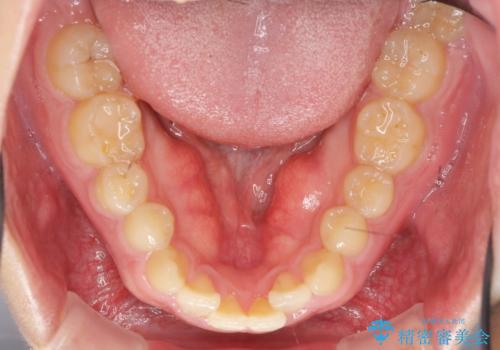

- 前歯の噛み合わせが反対になっていること、前歯の見た目の改善を希望され来院されました。

詳細な矯正検査の結果、顎の歪みが見られたため大きく歯を動かす治療ではなく前歯を主に並べることで前歯の前後関係を改善していきます。

前歯を主に動かす部分矯正であることからマウスピース矯正インビザラインによる治療を計画します。